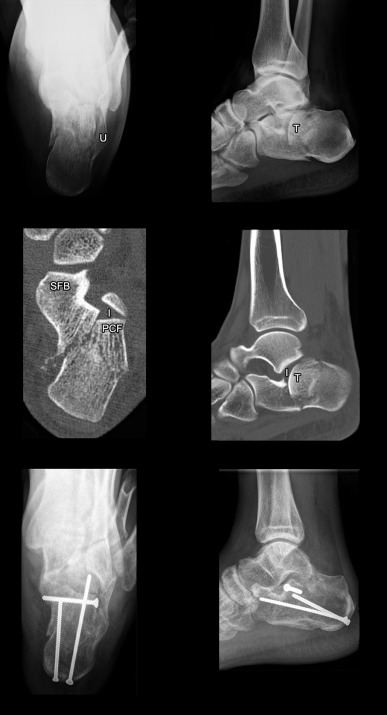

The fracture of subtypes B2 , was restored to obtain calcaneal morphology by the same surgical technique as subtype A2 . Additionally, the thalamic fragment was reduced via 4 cm incision sinus tarsi surgical approach and fixed with SF by screws. The subtype B4 were addressed percutaneously to obtain calcaneal morphology and congruent posterior subtalar joint via sinus tarsi approach. For severe subtype B4 , the reduction and casting were done as possible to obtain calcaneal morphology (Fig. 4 , Table 2 ).

Fig. 4

Fig. 4.

Subtype B2 intra-articular calcaneal fracture, calcaneal radiographs showed burst of lateral calcaneal wall (U) and a large thalamic fragment (T) created incongruent posterior subtalar joint (2 pictures above). CT images showed that subtype B2 comprised type B sustentacular fragment (SFB) and lateral posterior calcaneal facet (PCF) with intact articular surface (I) associated with burst calcaneal body by a large thalamic fragment (2 pictures middle). Percutaneous reduction and screw fixations were performed. Thalamic fragment was reduced and fixed by a screw via sinus tarsi approach (2 pictures below). Pre- and postoperative calcaneal fracture scores improved from 9 to 1 points.